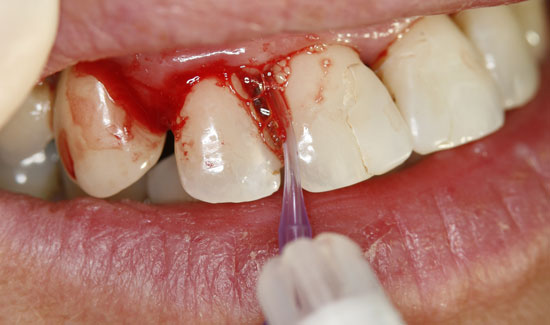

Abb. 3: Zustand nach Ozontherapie. Chlorhexidinverfärbung der Zähne

Als Ozongasspender verwendeten wir Prozone, das mit Hilfe von Kunststoffansätzen Ozongas schmerzarm in die Taschen einzuleiten erlaubt. Die lokale Ozongas-applikation wurde dreimal im Wochenabstand wiederholt. Außerdem wurde die Patientin auf notwendige persönliche Hygienemaßnahmen aufmerksam gemacht. Wir konnten nicht nur die Blutungen stoppen, sondern den Lockerungs-grad der Zähne in einem stabilen Zustand (2) halten und die messbare Taschentiefe verringern.